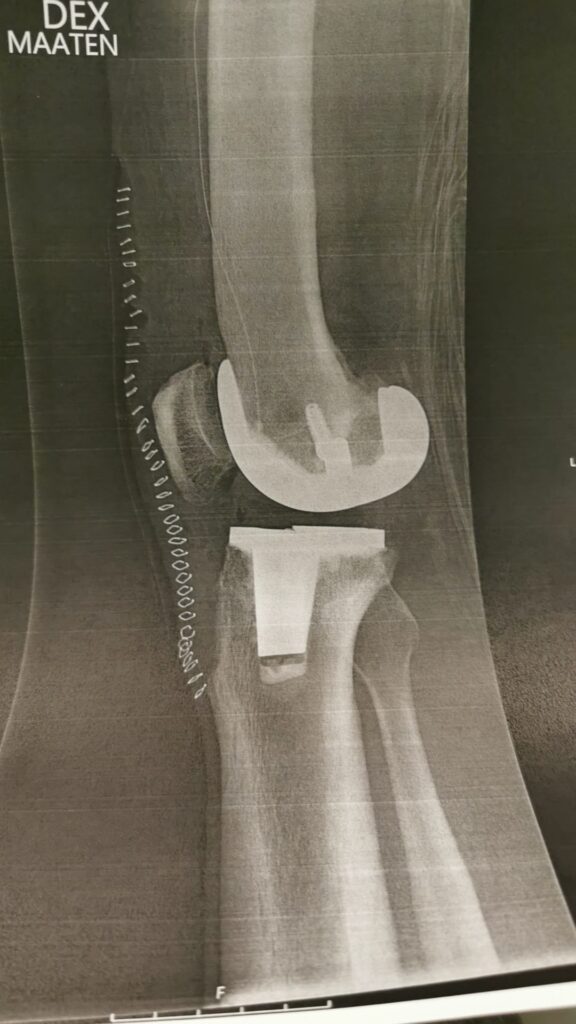

Viikolla 6 vuorossa oli jälkitarkistus ja tapaaminen Ortonissa, jossa käytiin läpi vielä aikaisempaa tarkemmin leikkaus ja sen kriittiset vaiheet. Pääsin myös samalla esittämään monia ortopedisiä kysymyksiä, jotka olivat mieltäni askarruttaneet. Polveni oli ollut normaalia haastavampi leikattava aikaisemman polvivammani vuoksi.

Polvi oli odotettua isompi työmaa kirurgille

Avaus siis tehtiin vanhaan arpeen joka oli muodostunut kolmen leikkauksen seurauksena. Sen iho on hyvin ohut ja vanhan avauksen kohdalla erittäin tiukasti faskiatasoon arpeutunut. Avauksen tekeminen vei rutkasti aikaa, mutta ihon ja faskian irrotus lopulta onnistui taitavalta kirurgilta!

Polvinivelessä oli runsaasti osteofyyttejä eli luupiikkejä ja polvilumpio oli tiukka eikä sitä saatu käännettyä. Paljastui myös että aikanaan korjattu etummainen nivelside oli toimimaton ja kutistunut olemattomaksi.

Sääriluun yläpinta oli lasimainen ja kun siihen sovitettiin tekonivelen komponenttia, luuhun kiinnitetty metallihakanen piti ensin saada ulos. Se vaati kohtalaista vaivannäköä ja talttaamista. Lisäksi sääriluun vinoutunut asento piti vielä korjata sahaamalla. Kun se oli tehty, komponentit asetettiin paikalleen, haava suljettiin ja haava suljettiin metallihakasilla. Onneksi olin unessa kaiken tämän aikana.

Kaikki edellä kerrottu tarkoittaa, että joudun kiinnittämään tavallista enemmän huomiota arven elastisuuteen. Todennäköisesti polvilumpion alaosaan jää joustamatonta ihoa, mikä näkyy hyvin myös videoissa. Ei tästä ihan täydellistä tule mutta toimiva kyllä. Vastuu on minun, ei muiden.